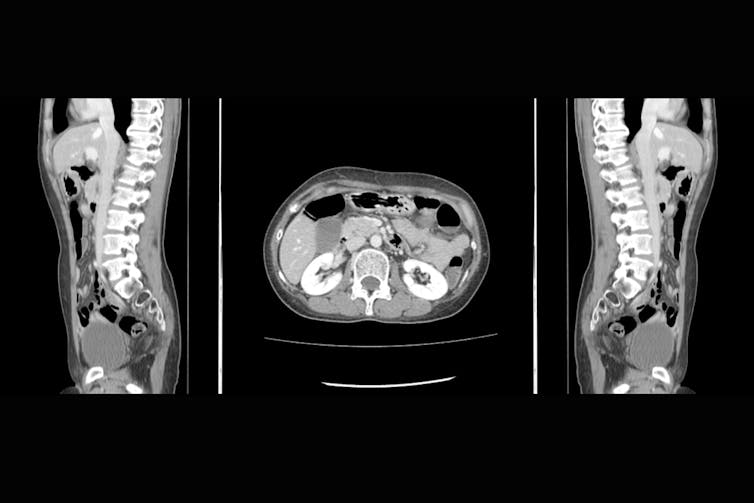

Newer medical imaging techniques such as CT scanning rely on Roentgen’s discovery, but instead of sending X-rays through the patient’s body from one direction only, beams are directed from many different angles, making it possible to create a much sharper two-dimensional image of the body’s interior.

CT scans now play a huge role in medical diagnosis. One recent study in a major emergency department showed that after a CT scan of the chest, the treating doctor’s leading diagnosis changes 42% of the time, and after a CT scan of the abdomen it changes 51% of the time. This is testament to the huge impact of X-ray technology on how medicine is practiced, sparing many patients unnecessary surgery and getting urgent treatment to others faster than would otherwise be possible.

When leading internists in the US were challenged to name the medical innovations without which it would be most difficult to imagine practicing medicine, CT scanning received the greatest number of votes by far.

Thanks to CT’s wide availability and great speed, doctors can determine within minutes whether or not a patient’s abdominal pain is due to appendicitis, chest pain reflects a tear in the aorta, or a severe headache is due to the rupture of a blood vessel in the brain. It is no wonder that about 80 million CT scans are performed each year in the US.